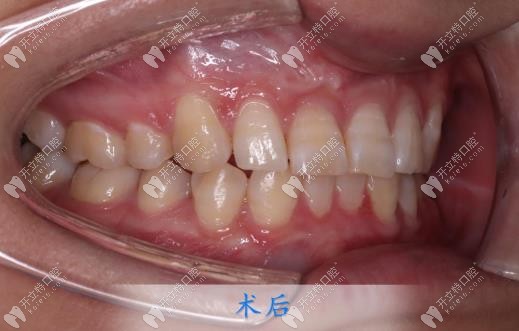

跑偏了,取下牙套后,牙齒的情況已經(jīng)全部改善了。但更讓我開心的是我的下巴,之前因為嘴巴導(dǎo)致下巴不明顯,矯正后下巴竟然有了,顏值也改變了好多,朋友見我都說我變好看了,但是又說不出來哪里變了!

都說牙齒矯正做好了堪比整容,我以前是真不信這句話的,直到自己親身經(jīng)歷,還是想給小伙伴們提個醒:找個認(rèn)真且負(fù)責(zé)的正畸醫(yī)生,真的可以省去好多麻煩!